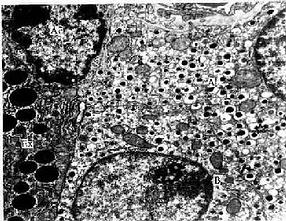

胰岛(pancreas islet)是由内分泌细胞组成的细胞团,分布于腺泡之间在(图13-4)。成人胰腺约100万个胰岛,约占胰腺体积的1.5%左右,胰尾部的胰岛较多。胰岛大小不一,小的仅由10多个细胞组成,大的有数百个细胞,也可见单个细胞散在于腺泡之间,胰岛细胞呈团索状分布,细胞间有丰富的有孔型毛细血管,细胞释放激素入血。人胰岛主要有A、B、D、PP四种细胞,某些动物的胰岛内还有D1细胞、C细胞等,细胞之间有紧密连接和缝隙连接。HE染色切片中不易区分各种细胞,一些特殊染色法可显示A、B、D三种细胞。近年多用电镜和免疫细胞化学法区分和研究胰岛各种细胞(图13-7,13-8)。

1.A细胞 约占胰岛细胞总数的20%,细胞体积较大,多分布在胰岛周边部(图13-7)。电镜下可见A细胞内的分泌颗粒较大,呈圆形或卵圆形,颗粒内的致密核芯常偏于一侧,膜与核芯之间在可见一新月形的帽样间隙,内含密度较低的无定形物(图13-8)。A细胞分泌高血糖素(glucagon),故又称高血糖素细胞。高血糖是小分子多肽,它的作用是促进肝细胞内的糖原分解为葡萄糖,并抑制糖原合成,故使血糖升高。

图13-8

2.B细胞 数量较多,约占胰岛细胞总数的70%,主要位于胰岛的中央部(图13-7)。B细胞内的分泌颗粒大小不一,其结构因动物种属而异,人和鼠等的B细胞颗粒内常见杆状或不规则形晶状致密核芯,核芯与膜之间有较宽的清亮间隙(图13-8)。B细胞分泌胰岛素(insulin),故又称胰岛素细胞。胰岛素是含51个氨基酸的多肽,主要作用是促进细胞吸收血液内的葡萄糖作为细胞代谢的主要能量来源,同时也促进肝细胞将葡萄糖合成糖原或转化为脂肪。故胰岛素的作用与高血糖素相反,可使血溏降低。这两种激素的协同作用,使血糖水平保持稳定。若胰岛素的作用与高血糖素相反,可使血糖降低。这两种激素的协同作用,使血糖水平保持稳定。若胰岛发生病变,B细胞退化,胰岛素分泌不足,可致血溏升高,并从尿中排出,即为糖尿病。胰岛B细胞肿瘤或细胞功能亢进,则胰岛素分泌过多,可导致低血糖症。

3.D细胞 数量少,约占胰岛细胞总数的5%,D细胞散在于A、B细胞之间,并与A、B细胞紧密相贴(图13-7)细胞间有缝隙连接。D细胞内的分泌颗粒较大,圆形或卵圆形,内容物呈细颗粒状,电子密度低。D细胞分泌生长抑素(somato statin),它以旁分泌方式或经缝隙连接直接作用于邻近的A细胞、B细胞或PP细胞,抑制这些细胞的分泌功能。生长抑素也可进入血循环对其他细胞功能起调节作用。

图13-7 胰岛

A.胰岛三种细胞分布模式图

B.高血糖素免疫细胞化学(PAP法)示胰岛A细胞 ×100

C胰岛素免疫细胞化学(胶体金法)示胰岛B细胞 ×100